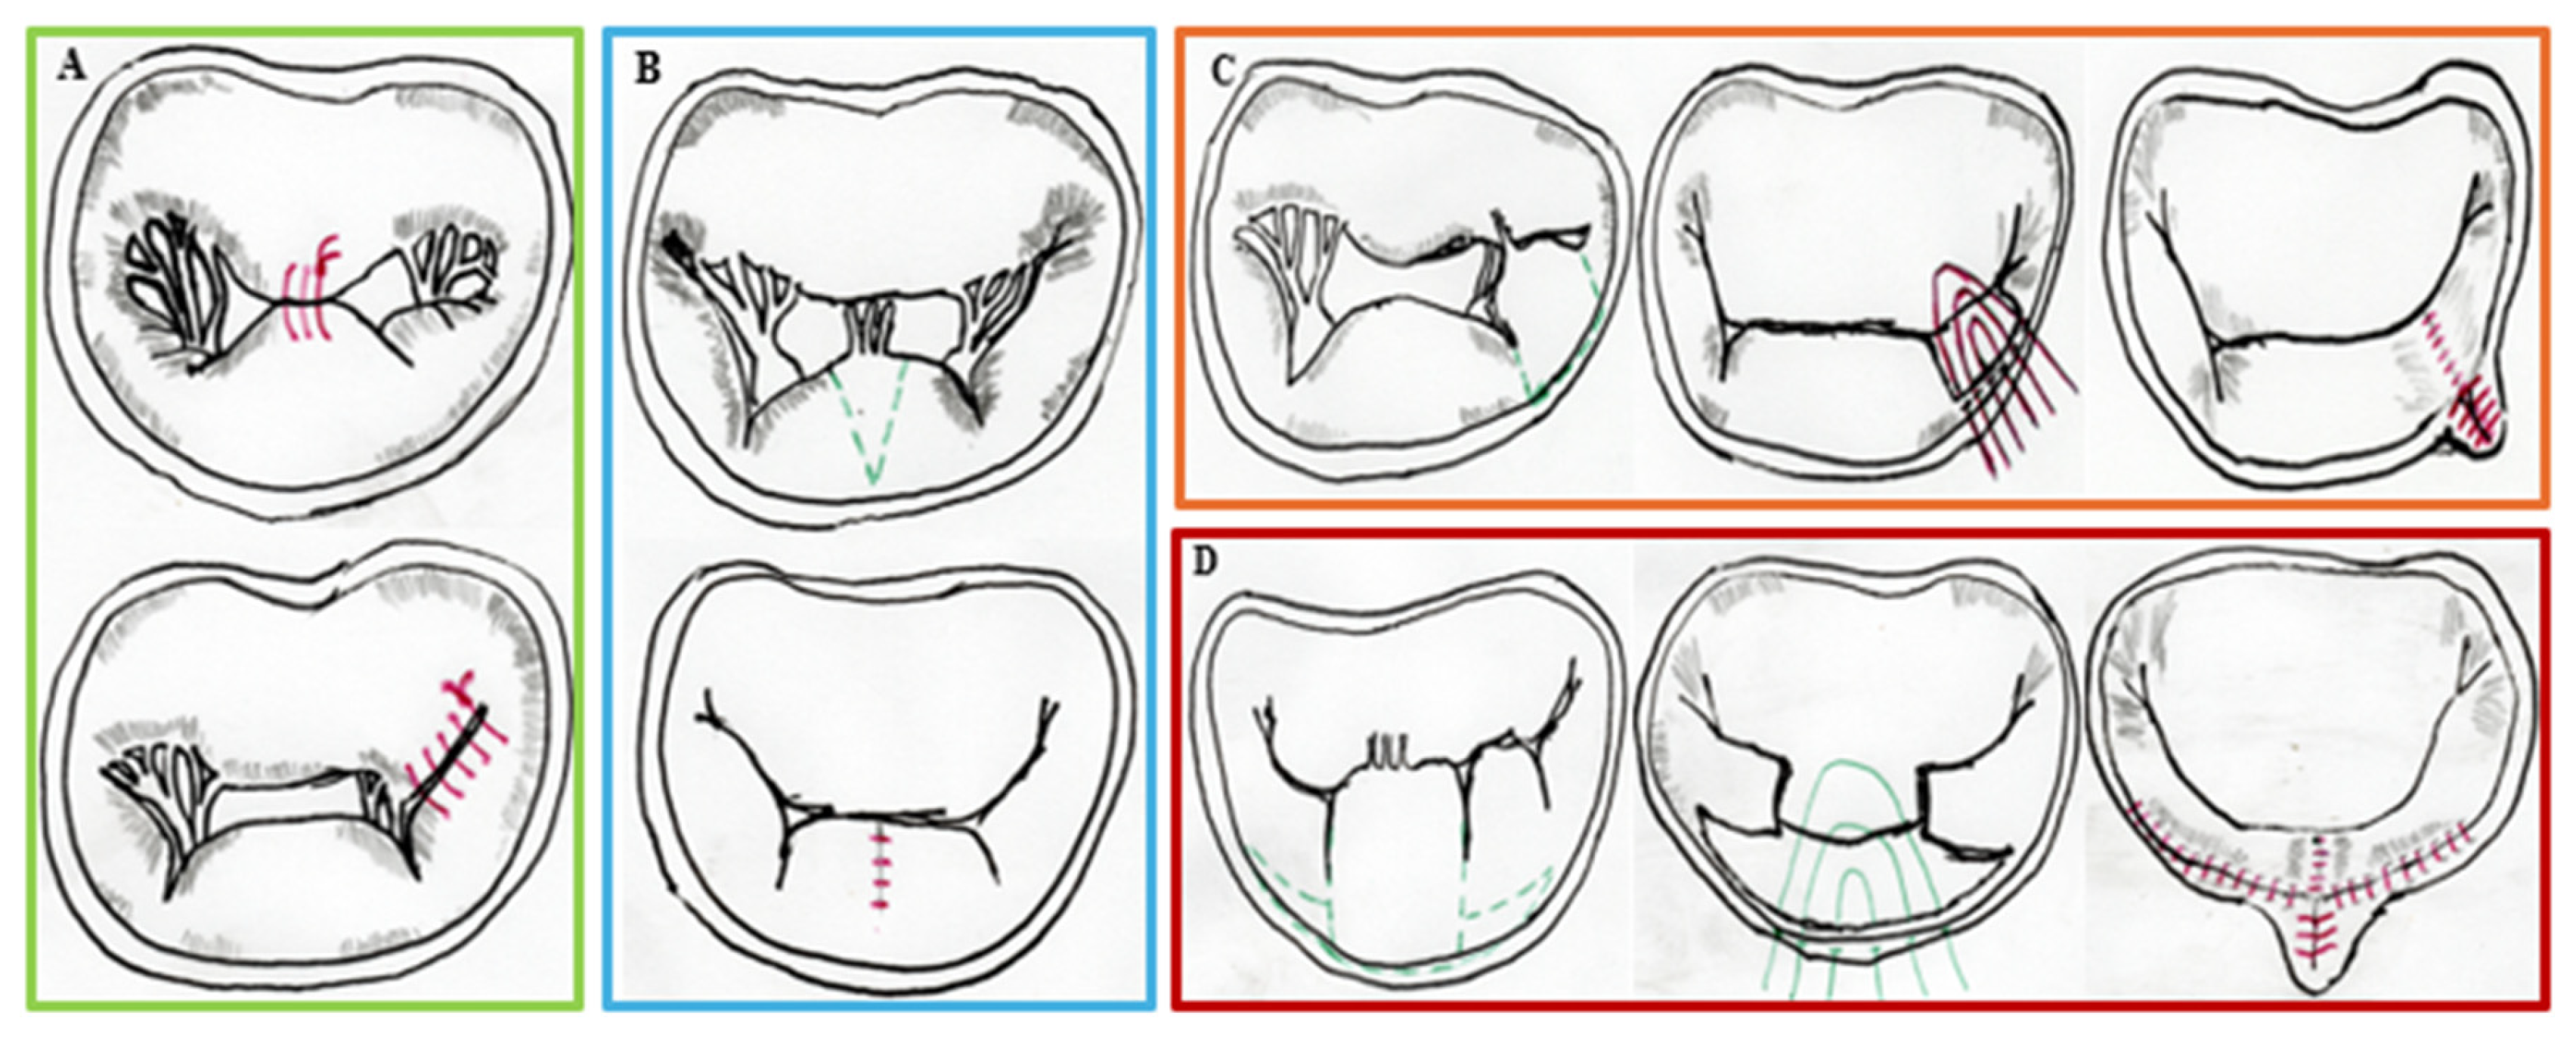

- Hameed, I.; Ahmed, A.; Waldron, C.; Algarate, P.T.; Kawczynski, M.; Fatima, M.; Alhazmi, A.; Colon, S.; Brackett, A.; Heuts, S.; et al. Mitral Valve Repair. JACC Adv. 2025, 4, 101589. [Google Scholar] [CrossRef]